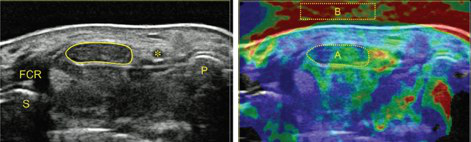

The simultaneous application of structural and functional imaging techniques is described as multiparametric (MP) (Fig. 9). Studies have shown that the MP approach results in greater diagnostic accuracy (Fig. 10).

The use of fusion imaging in uroradiology improves ultrasound lesion-detection rates, shows more reliable size controls at different time points, is an alternative to in-bore biopsies (Fig. 11) and can be used for focal therapy.